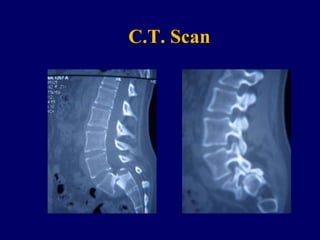

Mar. A.

Related to Isthmic Spondylolisthesis 4th – 5th degree

C.T. Scan